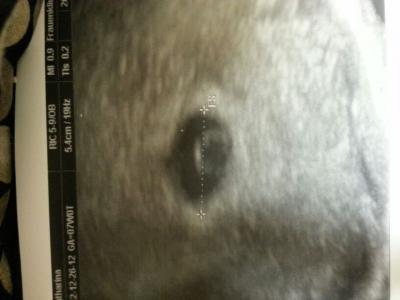

Ich weiß nicht wann ich mir ein Termin machen soll. Ab Morgen ist mein fa wieder da. Bin Morgen aber erst 6+0.. Ich weiß nicht ob man dann da schon den Herzschlag sehen wird. War vor einer Woche in kh da hab ich auch ein Foto mit bekommen bekommen(im Anhang) Glaubt ihr das man Morgen sehr viel mehr sehen wird?! Ich habe jetzt bis Nächte Woche Mittwoch frei, Vllt mache ich mir dann erst am Montag ein Termin... Ach ich weiß nicht, will einfach nicht vertröstet werden -.- Mag endlich meinen Mama-pass :)) Naja Sry fürs nerven. .. LG

Bild zu ab Morgen 7 Woche :) aber... - Forum für August - Mamis